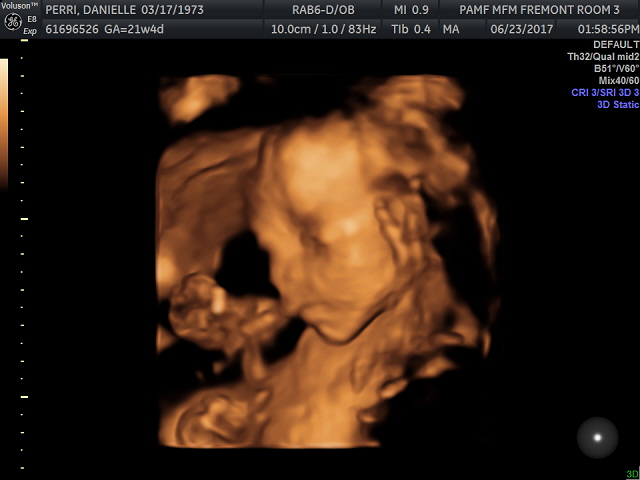

As the sonographer was unable to get all the pictures that we needed at my last anatomy screen appointment: a face profile and a few heart pictures, I had to have my second session today. The baby cooperated more than s/he had last time so she was able to get many of the heart ones right away. To my delight she also took some 3D ones letting me us see baby’s face and one hand for the first time.

The baby’s heartbeat was 139 beats a minute, a hair slower than 140 last visit and both within the healthy range. I even was given a photo of the heart chamber and the heartbeat pattern on the commemorative CD they gave afterwards.

Dr. D was the doctor this time and she said our baby was cute and healthy. As she had been told I was not choosing to learn the gender she did not look it up in my files so as not to accidentally tell me, which was sweet. Due to my age she recommended a follow up sonogram at both 30 and 36 weeks.